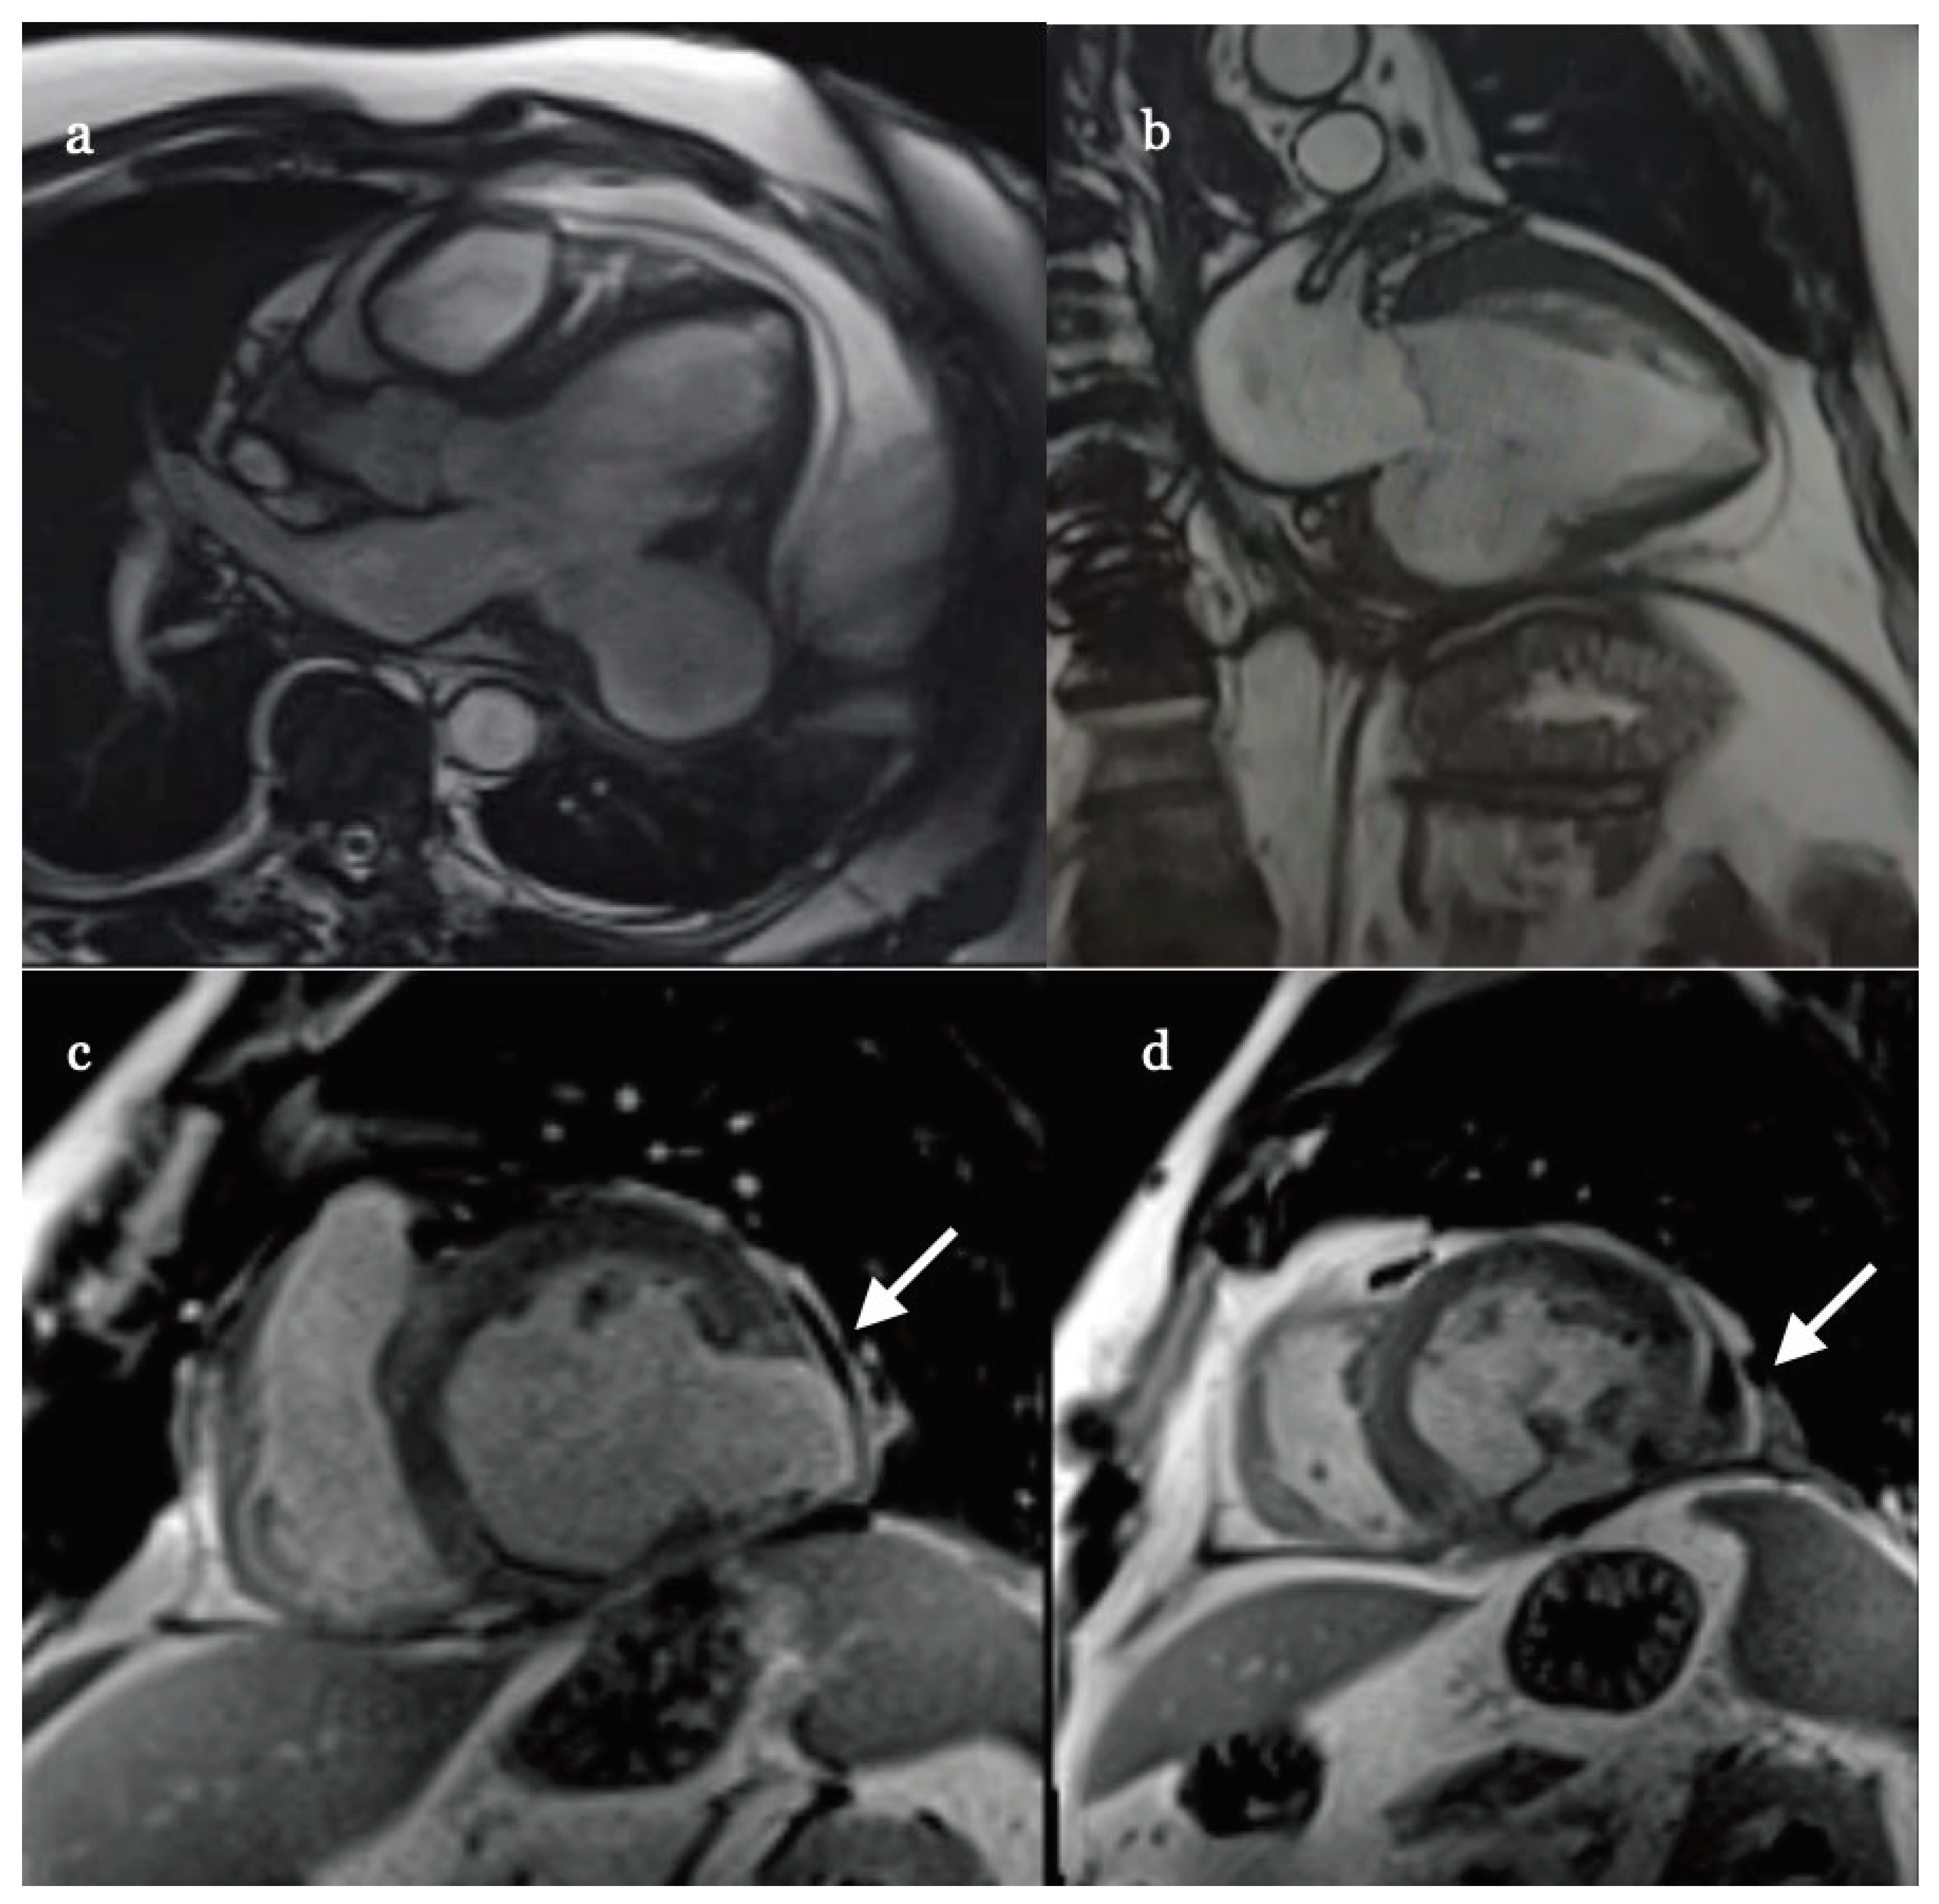

A month later the patient was electively re-admitted for cardiac magnetic resonance imaging (cMRI) which showed large (60 x 50 x 27 mm) and well-organized aneurysm but with further thinning (1 mm) of its wall (Figure 5 a-d). Because of continuing runs of ventricular rhythm on ECG Holter despite amiodarone oral therapy (Figure 6), signs, and symptom of heart failure in New York Heart Association (NYHA) II class, and no significant improvement of EF implantable cardioverter-defibrillator and dual chamber stimulator (ICD-DR) was implanted on that occasion as well.

Figure 5. MRI showing false aneurism in different projections: (a) 5-chambers; (b) 2-chamber; (c-d) short-axis where free wall rupture (white →) is best seen.